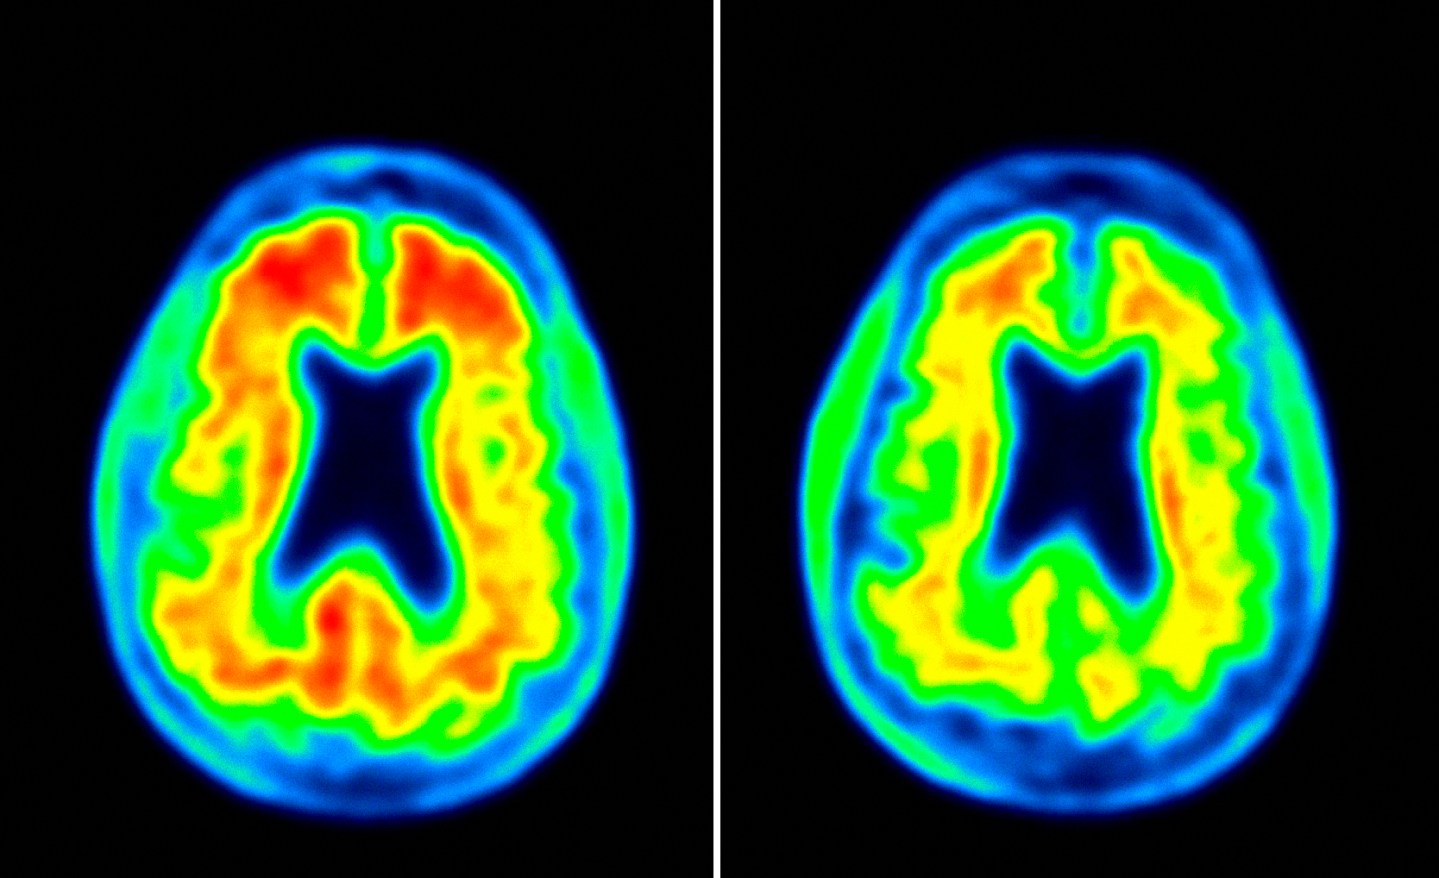

Verma, however, brought an important emerging technology into Biogen’s patient-screening process — imaging equipment that allowed clinicians to pinpoint amyloid (and more recently tau) deposits in the brain and to visualize the disease’s progression. The importance of this was much greater than it sounded. Of the patients who applied to join Biogen’s Phase 1 adu trial, an astounding 40% didn’t have the disease, despite showing signs of early dementia.

Biogen’s innovation was to pay for all this crazily expensive imaging in a Phase 1 trial, an early-stage study that is typically used to determine the proper dose of an experimental agent. In its adu trial, 166 patient volunteers underwent a battery of procedures — from multiple MRIs and glucose brain PET scans to lumbar punctures.

That’s why Biogen’s adu trial generated so much excitement. It showed that patients with mild—and even incipient (or “prodromal”) — Alzheimer’s could benefit from early therapy. Though the trial wasn’t designed to measure it, the drug appeared to slow the decline in Alzheimer’s patients’ recall and mental agility. After a year of treatment, trial volunteers who received the drug performed strikingly better on cognitive tests than the placebo group, though such results should be taken with a dose of caution given that the sample size was very small (and the tests themselves can be squishy). Nevertheless, the fact that this apparent clinical change was accompanied by rock-solid evidence of a biological change—a significant reduction in amyloid plaque — gave the finding some credibility.